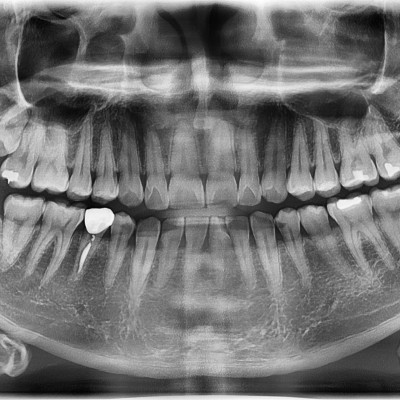

#18,28,38,48 사랑니 발치 #18,28,38,48 사랑니 발치 구강 외과 전문의가 당일 발치했습니다. --------------------..

작성자 이턱이 작성일 01-29 조회 9